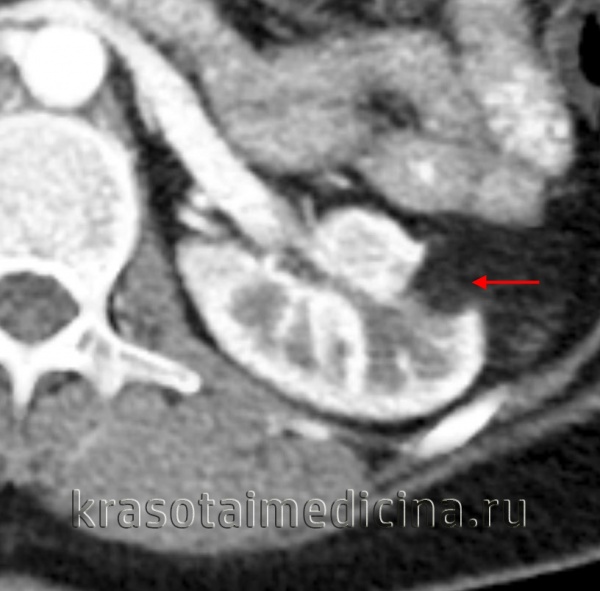

(Справа) КТ с контрастированием, аксиальная проекция: у пациента с туберозным склерозом выявлены двусторонние контрастируемые образования (АМЛ с отсутствием явного жирового компонента). (Слева) КТ с контрастированием, аксиальная проекция: ангиомиолипома (АМЛ) в воротах правой почки.

(Справа) КТ с контрастированием, аксиальная проекция: у того же пациента обнаружен очаг жировой плотности в просвете правой почечной вены. Такие признаки характерны для инвазии ангиомиолипомы (АМЛ) в почечную вену.